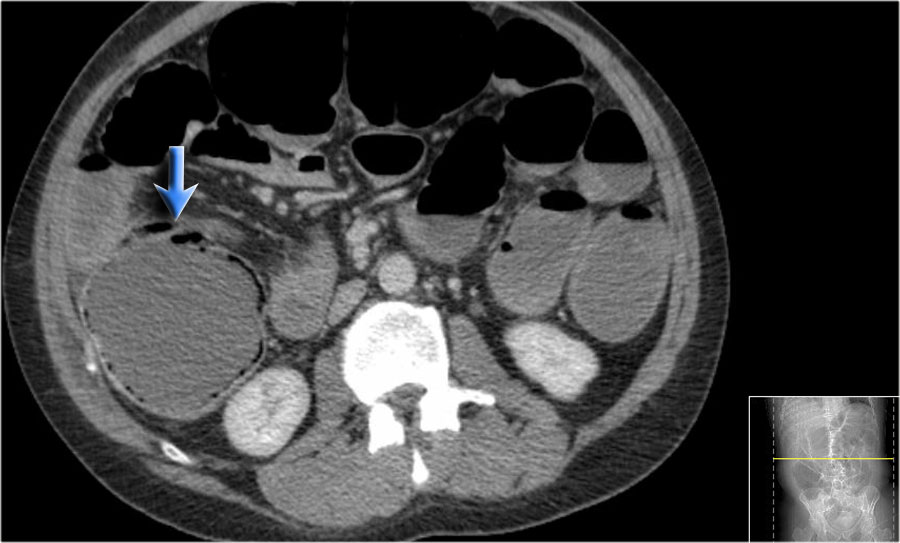

Đây là hình ảnh bệnh nhân thiếu máu cục bộ ruột do huyết khối tĩnh mạch mạc treo tràng trên – SMV (mũi tên đỏ).

Lưu ý tình trạng ứ máu tĩnh mạch trong mạc treo ruột (mũi tên vàng).